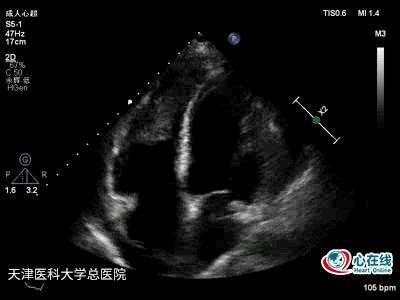

图3. 二维心尖四腔心切面示右心增大,右心室游离壁运动减弱,右心室内可见一巨大不规则中等回声团块,活动度小,与心肌分界不清,左右侧心包腔可见液性暗区。